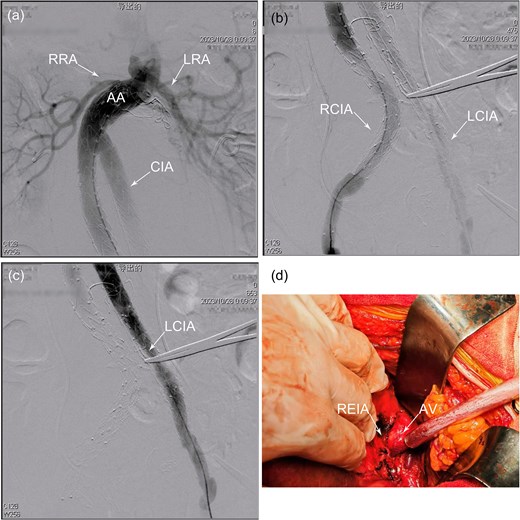

(a) Chest X-ray shows dextrocardia and dilation of the mediastinal shadow. (b) Contrast-enhanced computed tomography demonstrated a previous stent–graft placement, a type II endoleak with a giant aneurysm sac, a distal right common iliac artery dilatation with a type Ib endoleak. (c) Identification of a huge infrarenal aortic aneurysm through a mid-abdominal incision and was subsequently controlled with a sleeve to facilitate subsequent surgical procedures. (d) Angiography revealed a significant type Ib endoleak in the distal to the right common iliac branch. AA, abdominal aorta; CIA, common iliac artery; LRA, left renal artery; RRA, right renal artery; T1bEL, type 1b endoleak.

Following a comprehensive multidisciplinary consultation, a hybrid surgery approach was deemed the most appropriate strategy to address the complex ELs. Due to the patient's congenital anomaly, the patient–surgeon positioning was mirrored compared to a standard laparotomy setup. Under general anesthesia, a transperitoneal approach was utilized to access the giant infrarenal aortic aneurysm through a midline abdominal incision (Fig. 1c). Proximal aortic control was achieved using a nylon strap. Percutaneous access was then established via the Seldinger technique, through which a vascular catheter (DQ06112121S, Beijing Demax Medical Technology Co., Ltd.) was advanced into the femoral system. The catheter was subsequently exchanged for an extra-stiff guidewire (G4535, 0.035-inch, Cook Medical) and a 4F pigtail catheter (PV411038PIG, Merit Medical). Intraoperative angiography (Fig. 1d) confirmed the presence of a T1bEL within the right CIA. The right internal iliac artery (IIA) was patent, while the left IIA was not occluded. To address the T1bEL, a distal extension of the graft was deployed into the right external iliac artery (EIA) using Endurant II Stent Graft Systems (ETLW-16-16-C-93-EE&ETLW-16-16-C-124-EE, Medtronic).